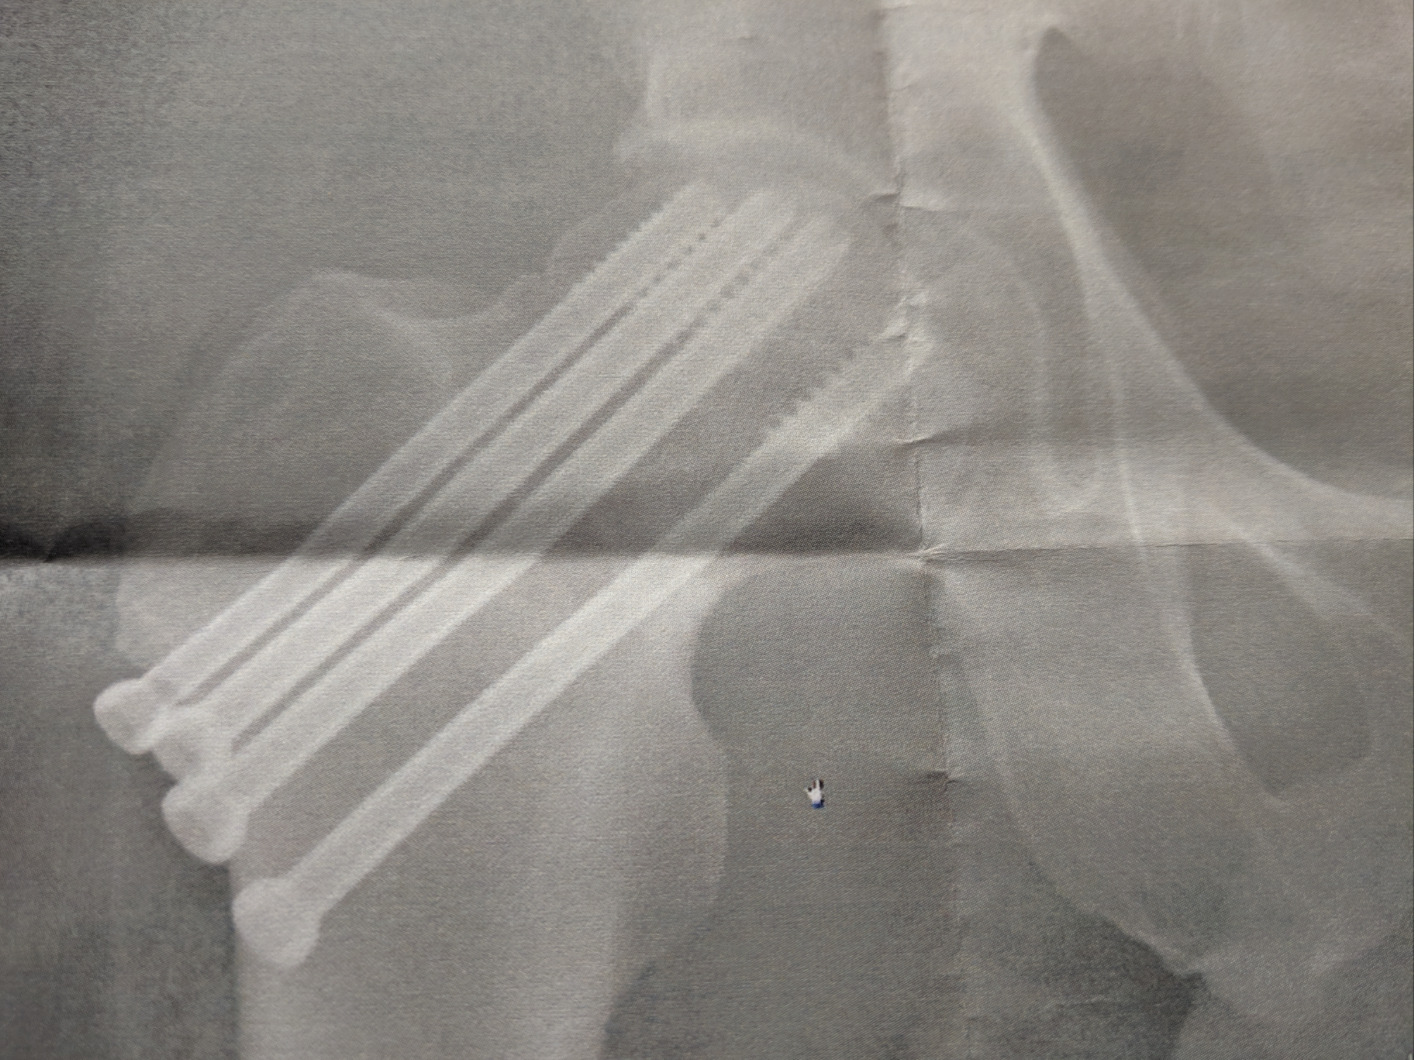

2019年交通事故後のピンを抜く手術

2019年6月に、交通事故で、右大腿頸部を骨折しました。

そのときは、緊急手術で、そのまま88日の入院。

そのときに、折れた右大腿頸部は、こういったピン(スクリュー)で固定していたのです。

最悪の場合、骨がくっつかず、再手術の可能性もありました。

骨がくっつかない場合は、人工骨頭という人工の骨を入れることになります。

人工骨頭だと20年に1回手術して取り替える必要があるとのこと。

残りの人生で、あと2〜3回は手術しなければいけません。

最初の手術から2年半。

今のところ、人工骨頭にはなっていません。

この2年半、診察を受け続け、経過を観察していたところ、骨もくっついてきたであろう(あくまで「あろう」)ということで、このピンを抜く手術をすることになりました。

ピンを抜く前の状況は、

・走れない(大きな衝撃をあたえないほうがいい)

・飛び降りられない(これも同様で。まあ、これは困りませんけど)

・右を下にして寝ると、まだ痛くなる(ピンが原因かはなんともいえず)

というもの。

普通にしていれば、まったく問題なく、自転車も乗れますし、娘をだっこすることもできました。

このままピンを入れたままという選択もあるのですが、異物でもありますし、抜けるなら抜いたほうがいいとのこと。

ピンを抜けば、「走れる」「飛び降りられる」ようにもなる可能性があります。

トライアスロンをやっていた私としては、スイム、バイク、ランができることが大事。

・ピンを抜く前→スイム・バイクは○、ランが✗

・人工骨頭になる→スイム・ランは○、バイクは✗(脱臼する可能性あり)

と、なかなか3つそろいません。

完全復活の可能性も考え、今回ピンを抜きました。

このピンが抜けるかどうかは確実ではありませんでした。

骨と融合しきっている、ピンが奥に入ってしまっている、ピンの頭がつぶれているなどといった状況も考えられます。

先生からも「無理に抜くことはしない」(デメリットもあるので)と事前に聞いていました。

長時間の手術になる可能性もあります。